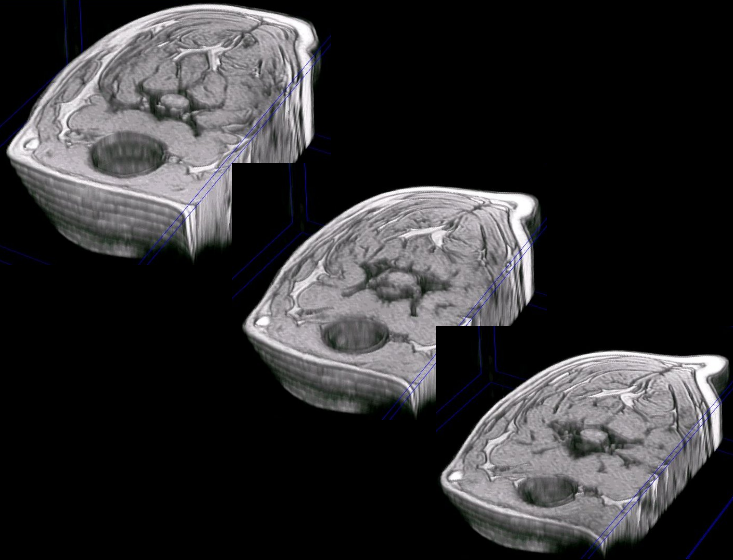

varias reconstrucciones del cuello del mismo paciente, a diferentes niveles |